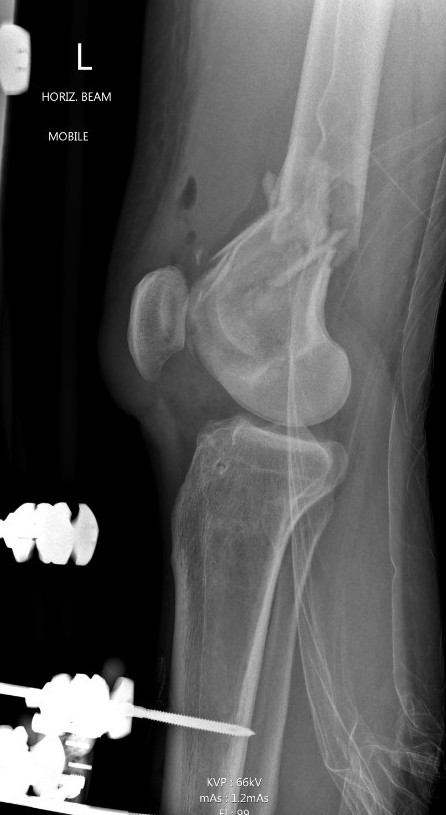

Type C: Complete articular

Xray / CT

Options